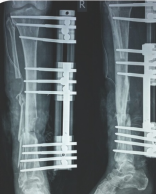

LRS is also used in deformity correction. But here instead of normal clamps swivel clamps are used. Here also you can do acute correction or gradual correction depends on the clinical situation